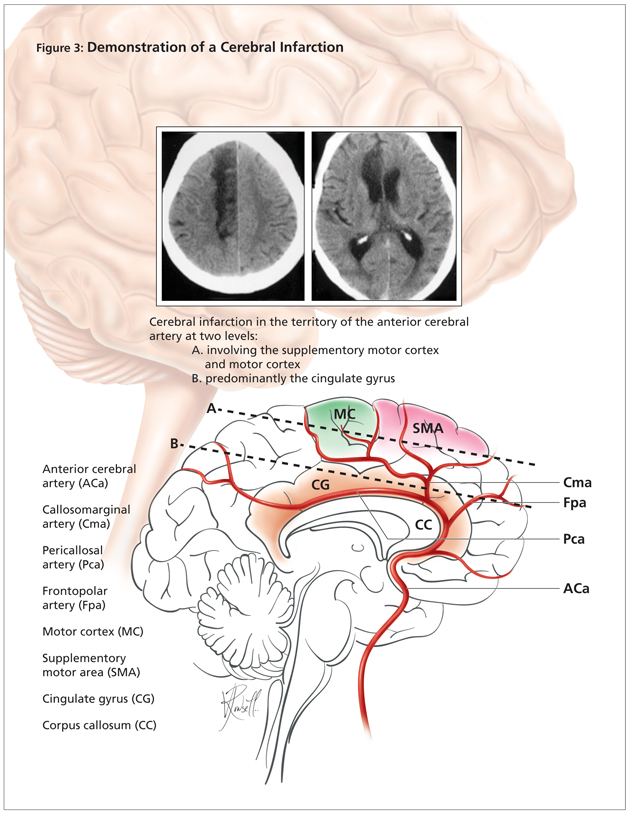

0808mutismfig3